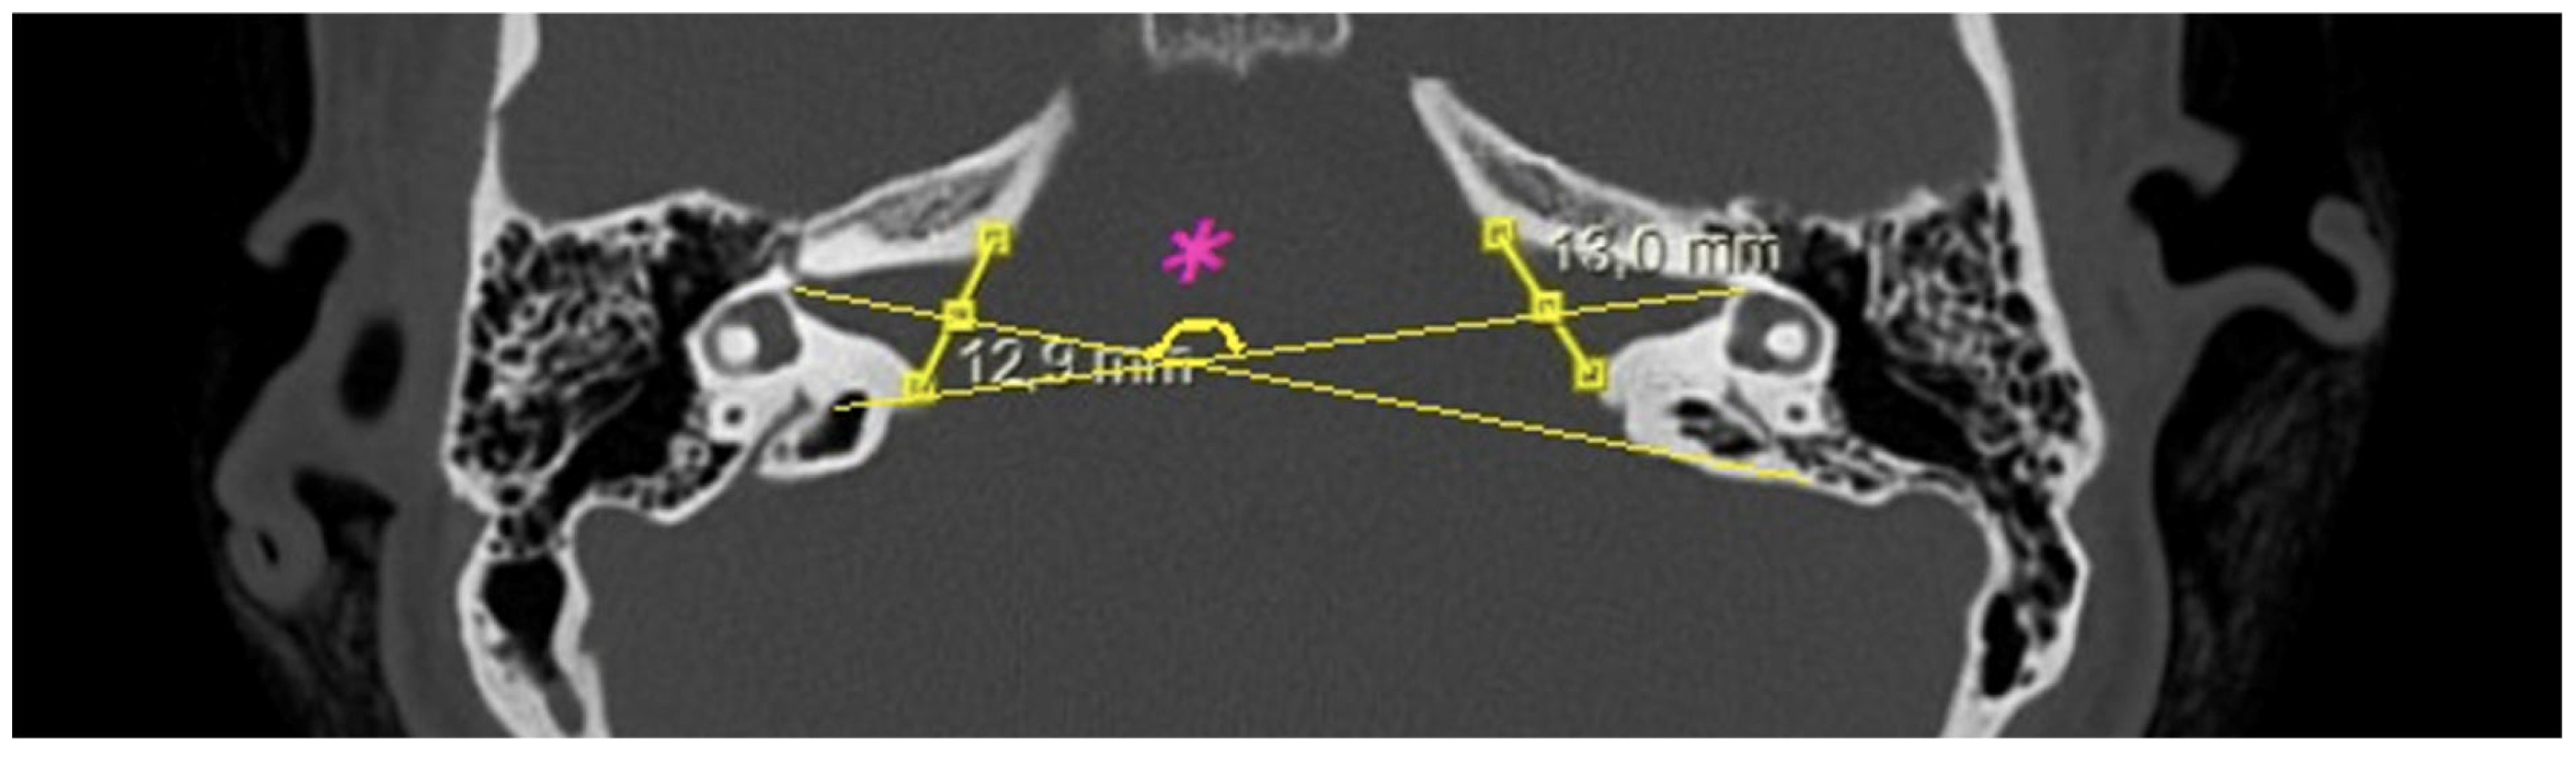

- Bitemporal distance: the tangential line passing posterior to the lateral semicircular canals, measuring the distance between the cortices of both temporal bones (Figure 1);